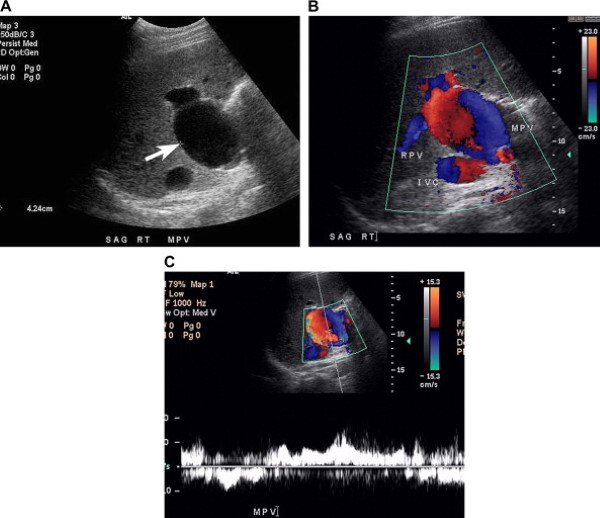

Dấu hiệu “âm – dương” của phình tĩnh mạch cửa

Phình tĩnh mạch cửa là một bất thường hiếm gặp, biểu hiện phình hình thoi hoặc hình túi với đường kính trên 2 cm, thường ở đoạn ngoài gan [20,21]. Phình tĩnh mạch cửa thường được phát hiện tình cờ. Vị trí thường xảy ra nhất là hội lưu tĩnh mạch cửa-tĩnh mạch mạc treo tràng trên và thân tĩnh mạch cửa trong rốn gan, phình ở chỗ chia ngành phải và trái ít xảy ra hơn [22]. Phình có thể là bẩm sinh, mắc phải trong tăng áp lực tĩnh mạch cửa, chấn thương, hoặc ghép gan.

Biểu hiện siêu âm của phình tĩnh mạch cửa bao gồm giãn tĩnh mạch khu trú hoặc khối dạng nang liên quan với tĩnh mạch. Trên siêu âm Doppler màu, phình tĩnh mạch biểu hiện dòng chảy rối hoặc hai chiều (Hình 10) [21].

Hình 10. Phình tĩnh mạch cửa ở bệnh nhân nam 22 tuổi đã được ghép gan 11 năm trước đây. (Hình A) Ảnh siêu âm thang xám phát hiện giãn khu trú thân tĩnh mạch cửa, đường kính chỗ lớn nhất 4 cm. (Hình B) Ảnh siêu âm Doppler màu cho thấy dòng chảy hai chiều bên trong chỗ phình mạch. Lưu ý ngành phải tĩnh mạch cửa có dòng chảy vào gan. (Hình C) Phổ tĩnh mạch trong túi phình. Túi phình đã ổn định và bệnh nhân được điều trị bảo tồn.